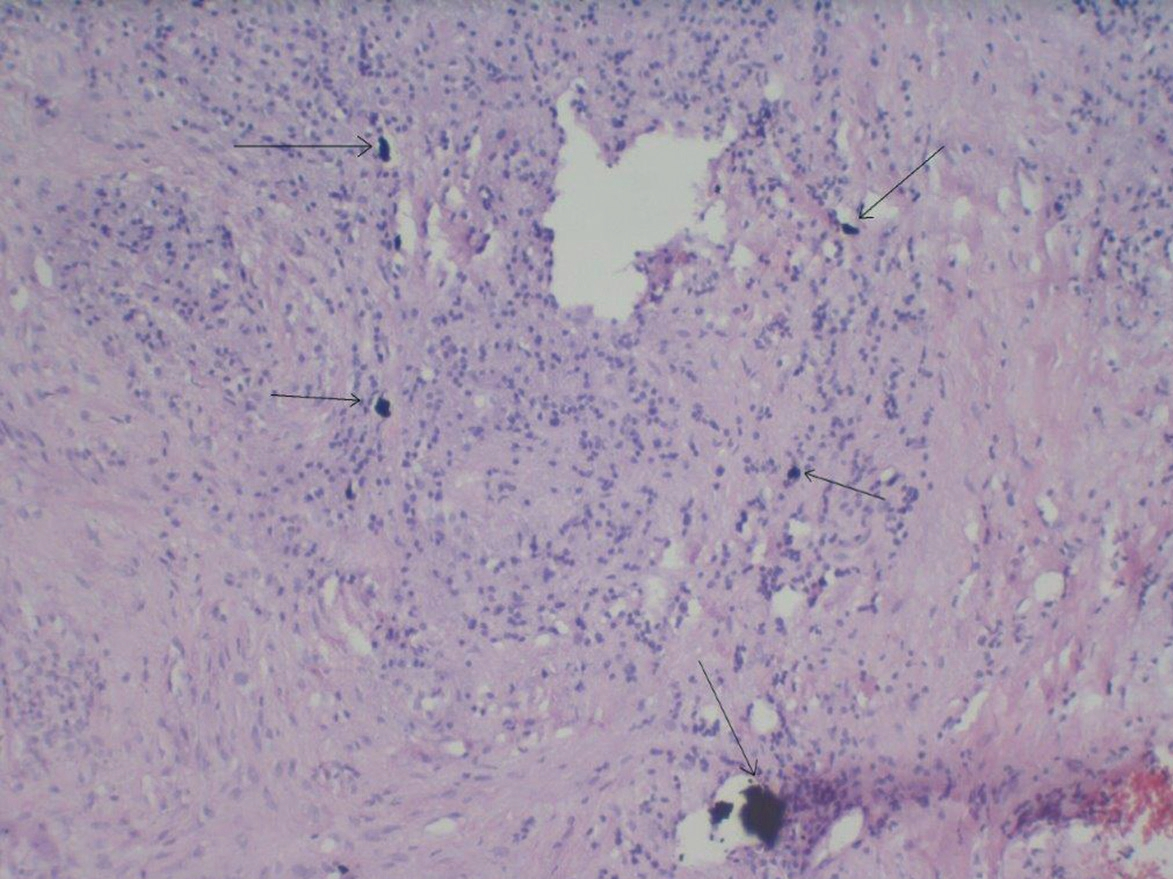

Wissenschaftliche Untersuchungen nehmen allerdings nun immer mehr die besonderen Eigenschaften des Implantatmaterials und seiner Oberflächenmorphologie in die Betrachtung. Als ein sehr oxidationsfreudiges Metall bildet Titan im physiologischen Milieu Oxidschichten auf seiner Oberfläche aus, die zur Passivierung führen und vor Korrosion schützen [17]. Einerseits fördert die Rauigkeit der Oberfläche die Osseointegration, anderseits begünstigt sie aber auch einen Partikelabrieb [18]. Seit zwei Jahrzehnten ist der wissenschaftliche Fokus auf die Auswirkungen von Titanpartikeln gelenkt, die sich durch mechanischen Abrieb beim Einbringen und durch korrosive Ereignisse (Bio-Tribocorrosion) von der Implantatoberfläche ablösen und als Mikro- und Nanopartikel immunologische Effekte im Organismus verursachen [19,20]. Titanoxidpartikel zeigen im Vergleich mit anderen Oxidpartikeln aus Aluminium- oder Zirkonkeramik eine deutlich höhere immunstimulative Potenz [21]. Makrophagen reagieren nach Kontakt mit Titanoxidpartikeln mit einer Ausschüttung der proentzündlichen Zytokine TNF-? und IL-1, was u.a. analog zur Pathogenese der Parodontitis eine Osteoklastenaktivierung und damit einhergehend eine Osteolyse zur Folge hat [22].

Korrosionsfördernde Faktoren sind mechanischer, chemischer und elektrolytischer Natur (Tribokorrosion). Bereits die mechanische Reibung beim Inserieren eines Implantates als auch Mikrobewegungen bei der Belastung führen zum Partikelabrieb, der im Nanometerbereich liegenden dünnen Oxidschicht am Implantat-Knochen-Interface und am Implantat-Abutment-Interface [23-25]. Im Vergleich von Implantatsystemen mit und ohne „platform-switching“ zeigten die letzteren eine höhere Partikelbeladung im periimplantären Gewebe. Die Ausprägung der ausgeschütteten Zytokin-Spiegel war proportional zur Gewebepartikellast. In radiologischen Kontrolluntersuchungen erwies sich deshalb das crestale Knochenniveau um Implantate mit „platform-switching“ im Verlauf als stabiler [26]. Erhöhte Partikelbeladung des Implantat umgebenden Gewebes findet sich auch nach Scaling-Maßnahmen an der Implantatoberfläche [27]. Die genannten Faktoren führen alle zu einer Partikeldissemination in umliegende und auf dem Blut- und Lymphweg in entferntere Gewebe und Organe. Mechanischer Abrieb und korrosive Prozesse verstärken sich dabei gegenseitig. Mit der elektronenmikroskopischen Spektroskopie (scanning electron microscopy-energy dispersive spectroscopy, SEM-EDS) gelang der Nachweis von Titannanopartikeln (NP) im periimplantären Knochen von Minischweinen. Der Vergleich verschiedener Implantatoberflächen ergab eine unterschiedliche Gewebebelastung in Abhängigkeit von Merkmalen wie Rauigkeit und mechanischer Verbundstabilität der aufgebrachten Oberfläche. Bereits am Tag nach der Implantatinsertion in den Kieferknochen der Versuchstiere waren Partikel im periimplantären Gewebe nachweisbar. Die Autoren schlussfolgern, dass mit der Zeit eine kritische Partikelbeladung im periimplantären Gewebe erfolgen könne, die eine Schädigung der Osteoblasten zur Folge habe [28].

Makrophagenaktivierung durch Partikelfreisetzung

Titan hat aufgrund seiner im Gegensatz zu anderen Metallen herausragenden Oxidationsfähigkeit in der Regel kein allergisierendes Potenzial, da es nicht als Ion, sondern als partikuläre Struktur in Geweben vorliegt und damit unter physiologischen Bedingungen primär keine T-lymphozytäre Reaktion auslöst. Stattdessen wird aufgrund des Partikelreizes das monozytäre Abwehrsystem aktiviert [29,30]. Dieser Vorgang führt zur Ausschüttung von proentzündlichen Zytokinen wie Tumornekrosefaktor- (TNF-?) und Interleukin-1? (IL-1?) durch Aktivierung der Monozyten/Makrophagen. Grundsätzlich aber führt die Partikelaufnahme durch die Makrophagen zu deren Aktivierung. Durch die permanente Partikelfreisetzung besteht der Entzündungs-initiierende Reiz fort, sodass ein empfindlicher Organismus dauerhaft proentzündlich getriggert wird. Der Pathomechanismus des Knochenabbaus durch die proinflammatorischen Zytokine TNF-? und IL-6 aufgrund von Makrophagenaktivierung durch Titanpartikel (MP, NP) aus Implantaten ist beschrieben [31]. Das Ausmaß der Aktivierung humaner Makrophagen wurde in-vitro gemessen und korreliert zum Ausmaß der gefundenen Zytokinausschüttung.

Die gesteigerte Abwehrreaktion von Gewebemakrophagen auf Partikel ist der zugrundeliegende Pathomechanismus für eine Titanpartikel-induzierte Entzündungsreaktion.